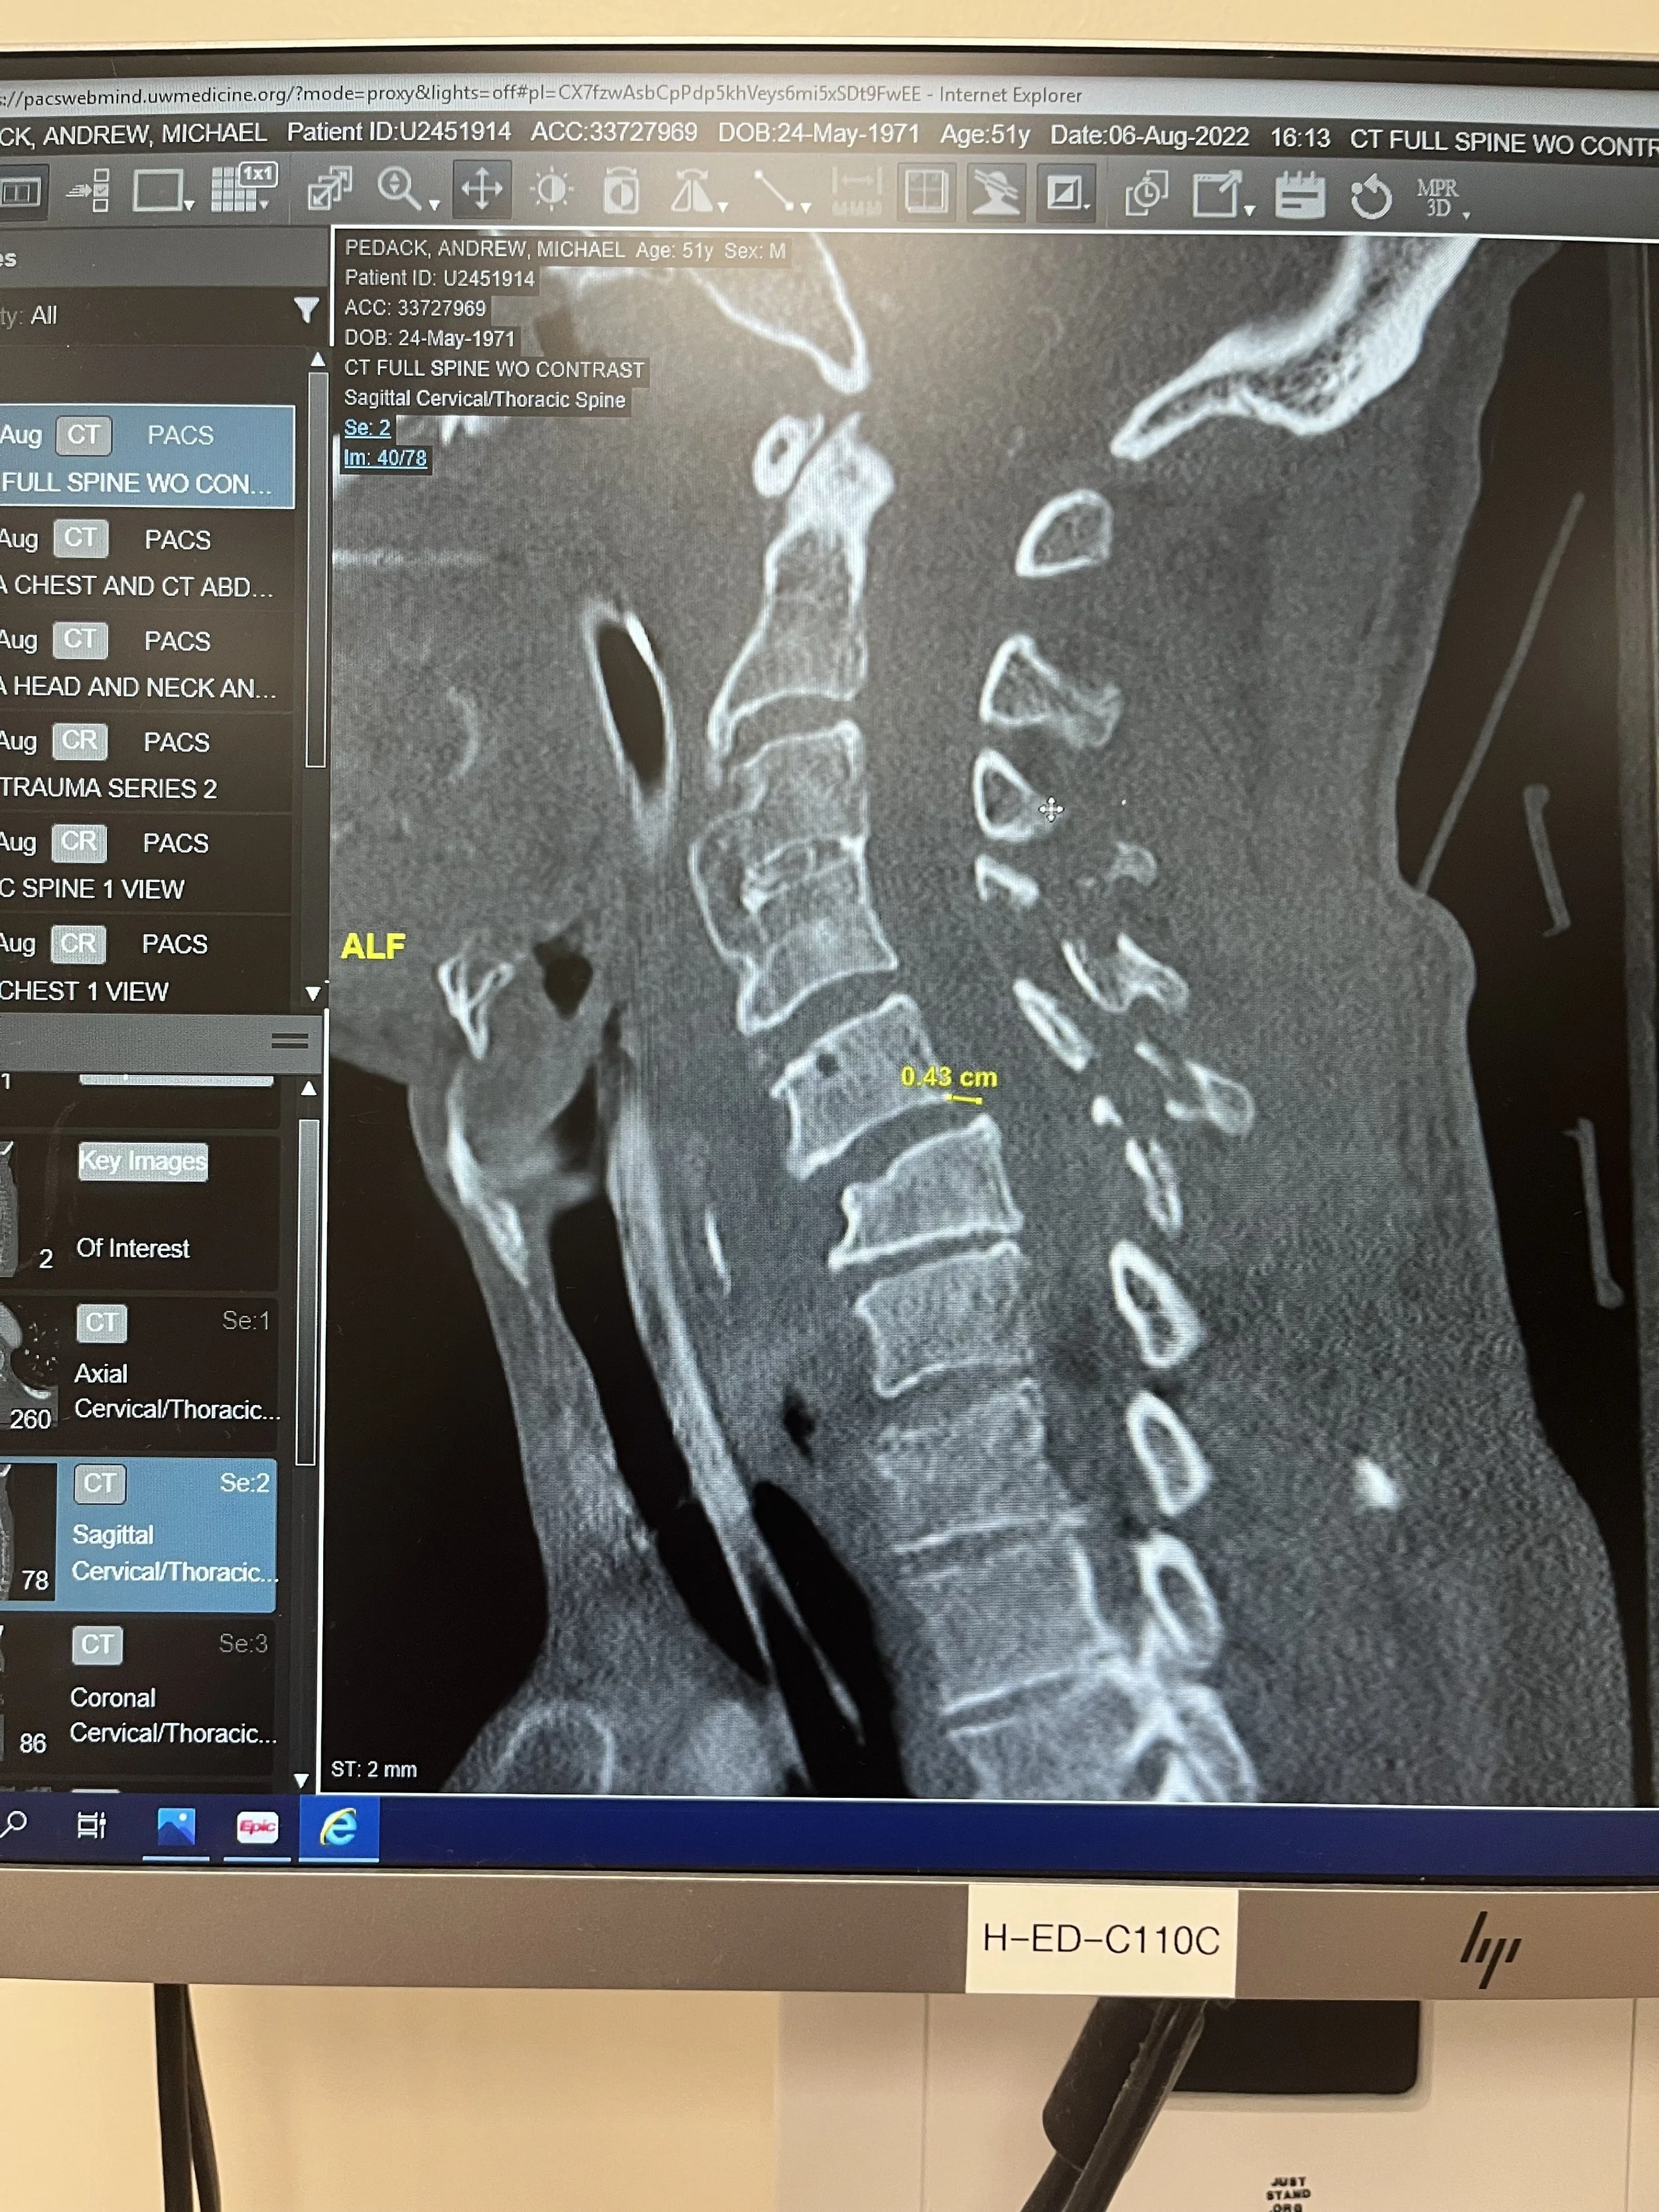

A dive from a bridge into shallow water left Andy with a shattered neck, resulting in a catastrophic spinal cord injury and paralysis from the shoulders down. In that moment, everything he had known about self-reliance, resiliency, independence, mobility, and possibility was just as shattered—but it also sparked a new vision that has continued to evolve.